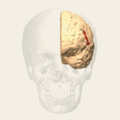

Brodmann area 44, or BA44, is part of the frontal cortex in the human brain. Situated just anterior to premotor cortex (BA6) and on the lateral surface, inferior to BA9.

This area is also known as pars opercularis (of the inferior frontal gyrus), and it refers to a subdivision of the cytoarchitecturally defined frontal region of cerebral cortex. In the human it corresponds approximately to the opercular part of inferior frontal gyrus (H). Thus, it is bounded caudally by the inferior precentral sulcus (H) and rostrally by the anterior ascending limb of lateral sulcus (H). It surrounds the diagonal sulcus (H). In the depth of the lateral sulcus it borders on the insula. Cytoarchitectonically it is bounded caudally and dorsally by the agranular frontal area 6, dorsally by the granular frontal area 9 and rostrally by the triangular area 45 (Brodmann-1909).